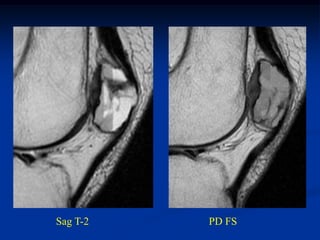

Sag T-2   PD FS